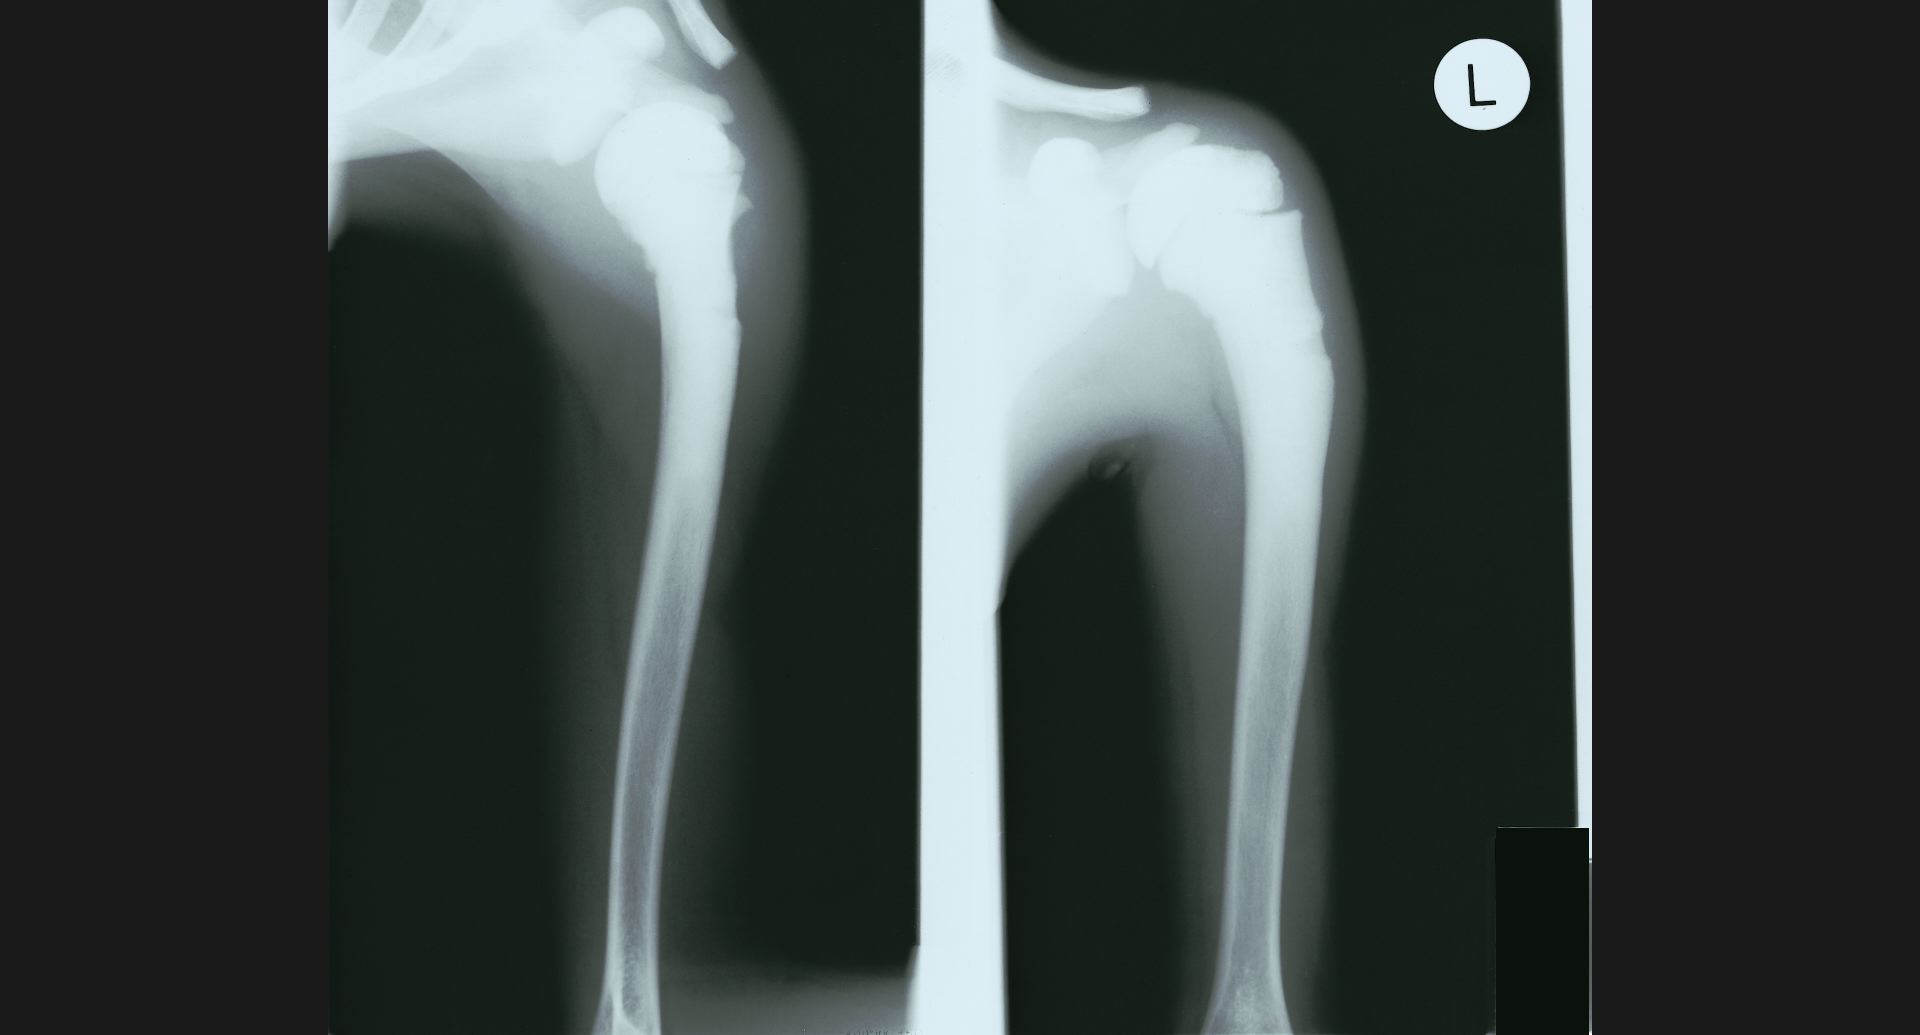

fig.18(70KB) :Marble bone

古い骨折部にも注目。